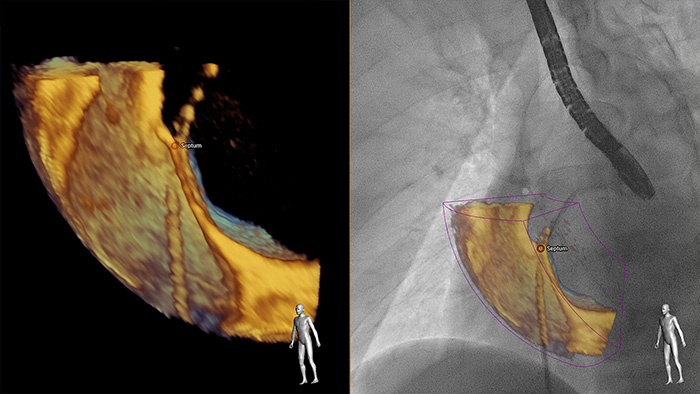

Smart Fusion bietet eine Darstellung mit hoher Detailgenauigkeit und trägt dadurch zu einer hohen Diagnosesicherheit bei. EchoNavigator überlagert Live 3D TEE und Live-Radiographie in Echtzeit und ermöglicht somit intuitive 3D-geführte Eingriffe.